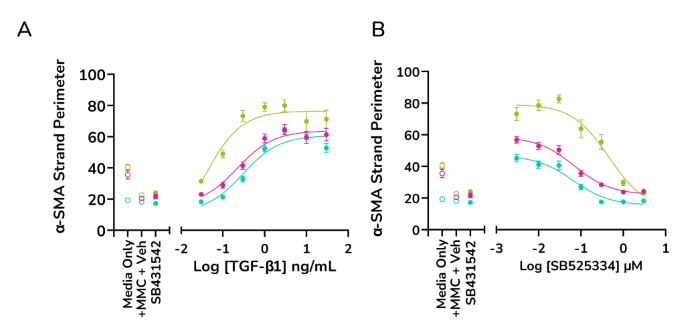

- Increased α-SMA strand perimeter

TGF-β1 dose-dependently increases α-SMA strand perimeter indicating increased contractile potential of activated fibroblasts, while ALK5 inhibitor SB525334 shows a decreasing trend (A&B) Data for α-SMA strand perimeter from three healthy human lung fibroblast donors. Image Credit: Newcells Biotech

Exposure to ALK5 inhibitors SB431542 and SB525334 reduces the effect of TGF-β1 at pathophysiologically relevant concentrations.